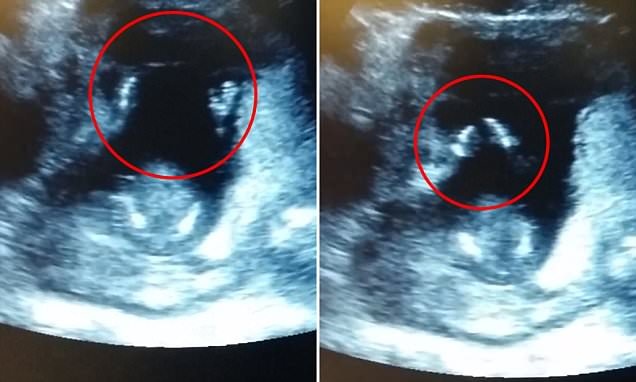

Hình ảnh cắt từ clip em bé vỗ tay trong bụng mẹ theo nhịp bài hát

Clip em bé 14 tháng tuổi vỗ tay trong bụng mẹ

Mẹ của bé, chị Jen Cardinal, sống ở Anh, cho biết em bé được 14 tuần và họ phát hiện ra cảnh tượng rất thú vị này khi đi siêu âm thai. Chồng cô chính là người quay phim.

Đoạn clip được tung lên YouTube ngày 26/3, em bé còn vỗ tay theo giai điệu bài hát: “If you’re happy and you know it clap your hands…” (Nếu bạn vui và bạn biết điều đó thì hãy vỗ tay…).

Thật ra đó là chỉ là thủ thuật tua đi tua lại đoạn clip quay cảnh siêu âm của cặp vợ chồng dưới sự hỗ trợ của bác sỹ. Sau khi phát hiện đứa trẻ vỗ tay ba đợt, vị bác sỹ siêu âm đã tua lại đoạn phim đó, canh giờ để lồng bài hát vào đúng lúc đứa trẻ vỗ tay. Trong khi đó, người cha quay phim và sau đó đưa lên mạng.

Dù sao, một thai nhi 14 tuần tuổi vỗ tay trong bụng mẹ đã là chuyện quá hiếm nên clip này đang "làm mưa làm gió trên mạng". Đoạn video dài 15 giây đã thu hút hơn 48.000 lượt xem.